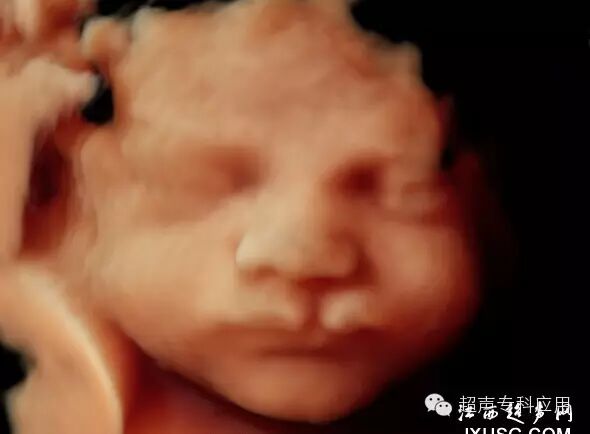

1.1 表面结构的成像 这是三维超声最初在胎儿显像的应用。早孕期可显示整个胎儿的形态以及头颅、腹壁、四肢等;中孕期则能显示胎儿头面部、手指(脚趾)等相对细小的结构。这些表面结构的三维图像,客观逼真,一旦存在胎儿体表的畸形,如唇裂、脑膨出、脊柱裂、脐膨出、腹裂、肢体或手脚畸形,三维成像能够让孕妇及家属一目了然,让产科医生或儿科医生更结合实际情况进行咨询,方便选择下一步的处理方案。虽然三维超声对体表畸形的诊断可能并不比二维超声提供更多信息,这些体表畸形可能在二维声像图上也较容易显示,但孕妇及家属却不理解二维图像,难以想象畸形外观如何、有多严重。为了更人性化的服务,目前,也有不少医院或产院对孕妇提供“胎儿照相”;四维超声观看胎儿运动并录像,以留作纪念。三维表面成像的重要条件是感兴趣区域前方一定要有足够的羊水,而且不能被肢体、脐带等遮挡。羊水过少或晚孕期胎儿充满官腔时,三维表面成像则有较大困难。

胎儿唇裂表面三维成像